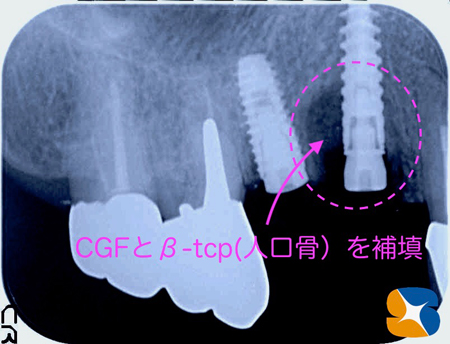

抜歯を終えた後、腫瘍の排除を徹底的に行うと、骨が大きく欠落していることが分かりました。この菲薄な部分にでも当院ではインプラントの移植と骨の補填を行います。

患者様の血液を採取して、傷口の復元には欠かせないコラーゲンの塊を僅か15分で作ります。これをインプラント周囲に盛り足すことによって、インプラント周囲に骨と歯肉を短期間で復元させています。

右側:ノーベルバイオケア社:アクティブ直径3.5 × 15㎜

左側:オステム 社:TSⅢ SA 直径4.0 × 11.5㎜